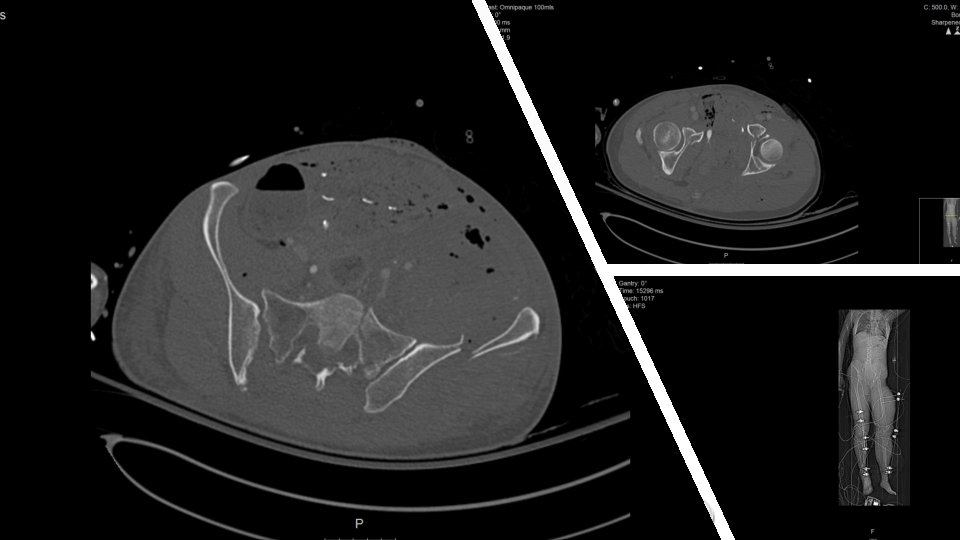

CASE 1: Cyclist runover by cement truck HR 128 BP Unrecordabl e p. H

CASE 1: Cyclist runover by cement truck HR 128 BP Unrecordabl e p. H 6. 759 Lac 9. 4 Sats 60%

KEY MESSAG E CASE 1 1 Right turn resus 2 3 Damage control orthopaedic

KEY MESSAG E CASE 1 1 Right turn resus 2 3 Damage control orthopaedic s Pelvic infected soft tissues can kill